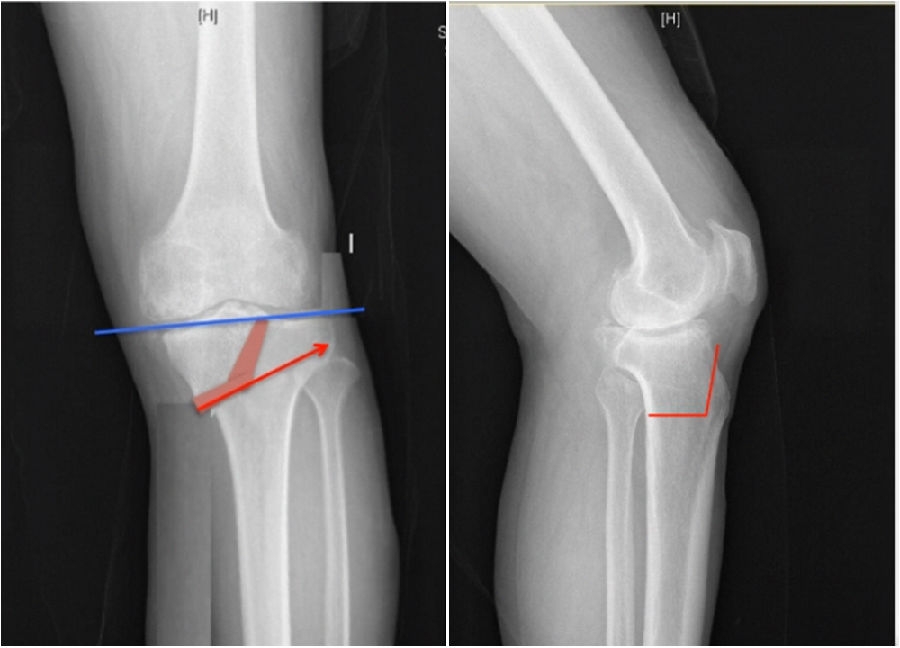

通过MAT测量全长片和内外侧应力位片,可以明确的测量出畸形的来源是股骨还是胫骨,有没有关节内磨损和韧带松弛。

MCOA病例,对线异常来源多个因素:胫骨畸形(MPTA异常),股骨形(mLDFA异常),胫骨平台塌陷,LCL松弛,内侧关节软骨丢失造成关节线不等宽等。MAT可以确定其中每种成分;应力下拍片,确定JLCA的关节松弛成分。关节软骨丢失占JLCA 3度,LCL松弛占JLCA 4度。

2、如何根据内侧间隙确定目标力线?

根据膝关节内侧间室模式程度选择个体化的目标力线。

关节间隙正常:目标MAD=0

关节间隙减少1/3:目标MAD =1/3Fujisawa

关节间隙减少2/3:目标MAD =2/3Fujisawa

关节间隙消失:目标MAD =3/3Fujisawa